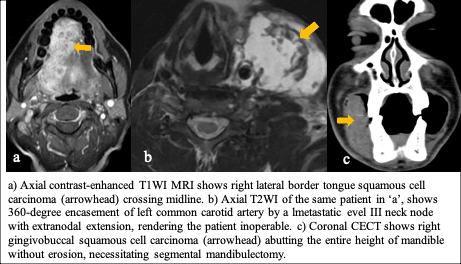

Role of imaging: Surgery is the mainstay of treatment for oral cavity cancers provided there are no contraindications on imaging. Mucosal lesions are directly visualised by the surgeons, however, the role of imaging lies in delineating the submucosal and the entire extent of the lesion, providing information on perineural spread, extent of bone involvement, degree of vessel encasement, status of cervical lymph node, and possible infiltration of prevertebral fascia. Oropharyngeal cancers, on the other hand, are usually treated with chemoradiotherapy, for which, delinating the entire extent of lesion on imaging along with staging, are crucial. However, T1/T2 non-midline cancers are amenable to transoral robotic surgery (TORS), provided there is no infiltration of superior pharyngeal constrictor muscle or parapharyngeal space, and there is no medialization of internal carotid artery.